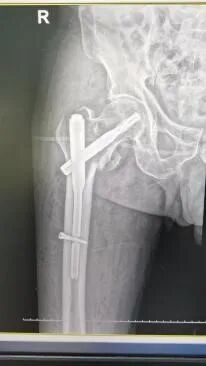

手术治疗:股骨转子间骨折闭合复位髓内钉内固定术。

股骨转子间骨折的手术治疗方法首选内固定手术,适用于大多数老年髋部骨折患者,骨科(创伤中心)熟练开展此类手术,具有创伤小,出血少,手术时间短(手术时间在30-60分钟),曾成功为104岁老人手术!做到了用微创解决骨折问题,术后第二天患者就可以下地做早期康复训练,有效地避免了卧床并发症,大大提高了病人的生活质量。

图片图片